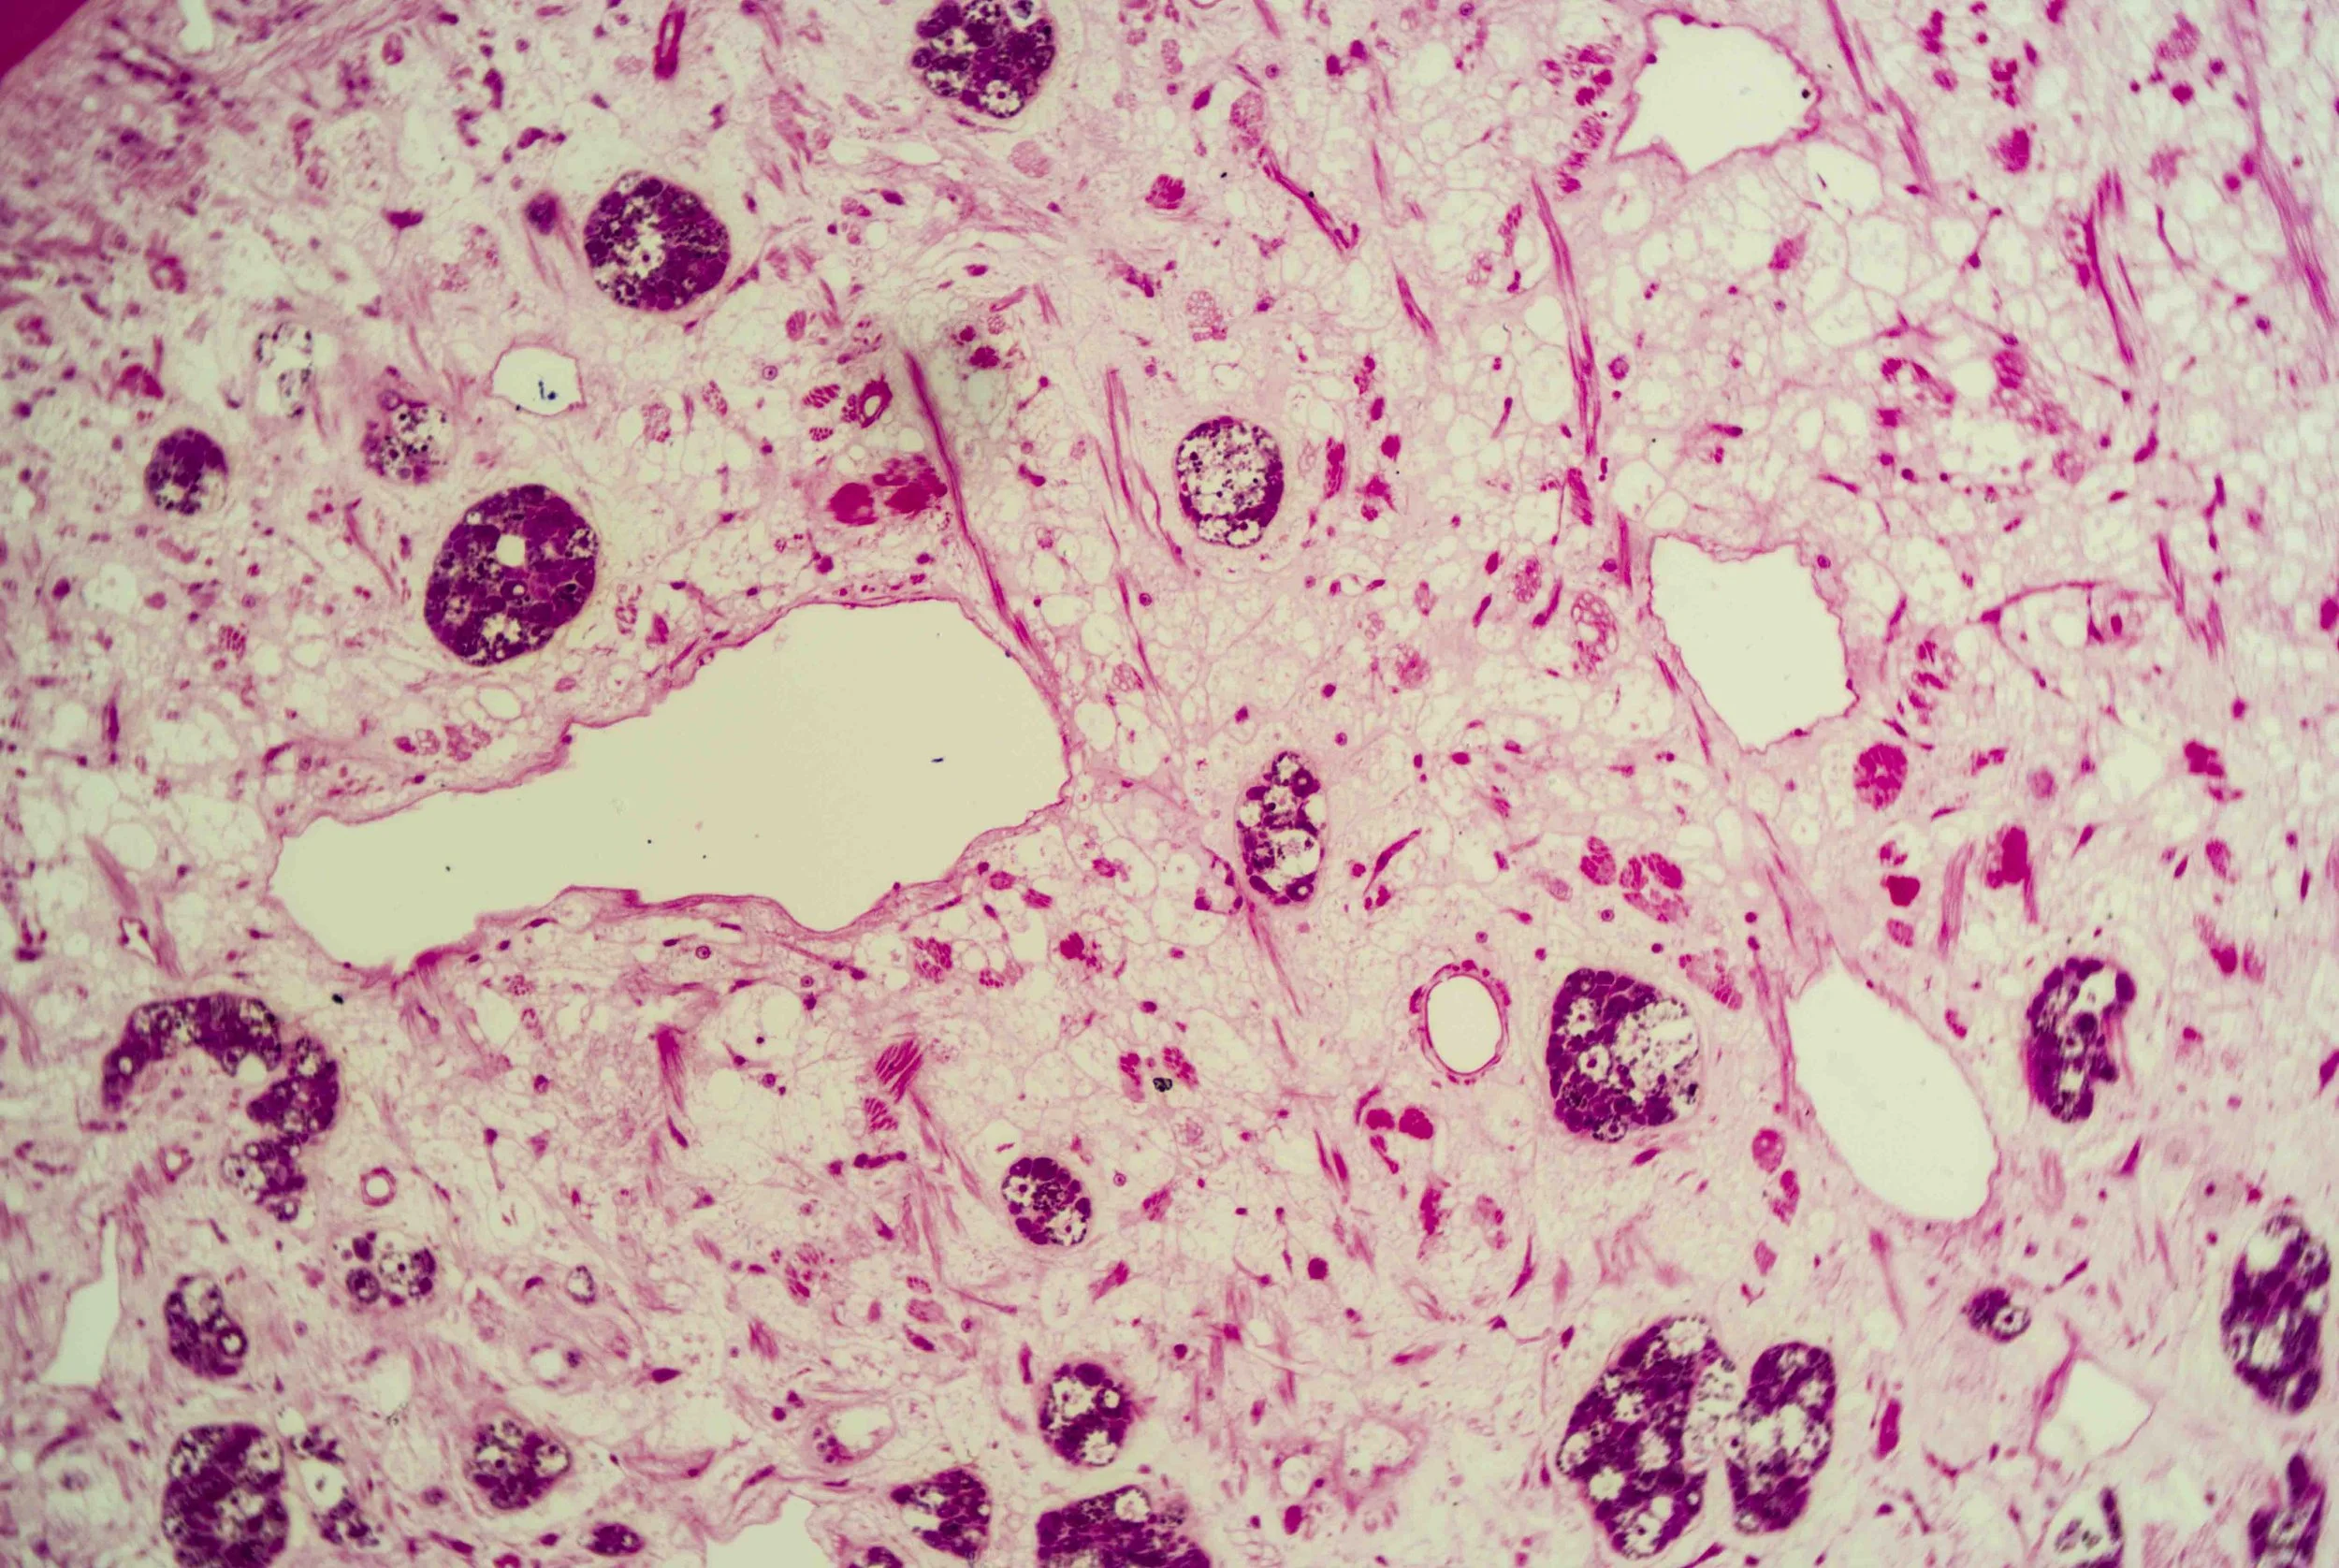

At first glance, a liver fluke is a simple, leaf‑shaped flatworm. Under magnification, however, a cross‑section reveals a labyrinth of chambers and cells, like stained‑glass windows filled with pink and purple mosaics. These sections show the parasite’s densely packed tissues, reproductive organs and digestive sacs nestled within its protective tegument.

Unlike many animals, liver flukes lack an anus; their branched gut empties through the mouth.

Liver flukes are hermaphrodites, carrying both male and female reproductive organs. They feed primarily on blood within the host’s liver and bile ductsen.wikipedia.org, and their branched intestine distributes nutrients throughout the body.

These parasites cause fasciolosis in livestock and humans, a disease that can lead to fever, abdominal pain, jaundice and anaemia. Chronic infections with certain species, such as Opisthorchis viverrini and Clonorchis sinensis, are linked to long‑term inflammation and increased risk of bile‑duct cancer.

Yet there is an eerie beauty in their design. The intricate patterns seen in histological sections hint at the fluke’s complex adaptations—suckers, tegument, branched gut and prolific reproductive tissues—all evolved to exploit its ecological niche.